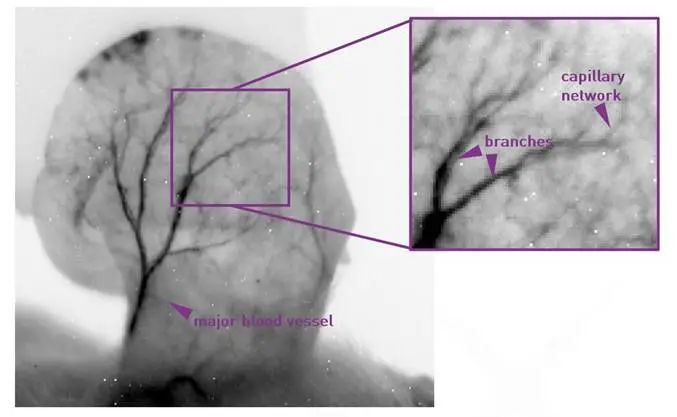

使用更高放大倍数的镜头可以获取特定感兴趣区域的更详细视图。以下展示的是耳朵脉管系统的示例。采集参数包括:500ms的积分时间、2FPS的帧率、高增益以及CDS模式。为了提高对比度,进行了灰值反转,未进行其他图像处理。值得注意的是,高信噪比和信号背景比可以使皮肤和皮下血管显现出来。

例如,在制药应用中,这种技术可以实现非侵入性的研究由敏感材料诱导的血管反应,提供更加精准和清晰成像结果。

图6-红外Ⅱ区外耳脉管系统的荧光体内成像